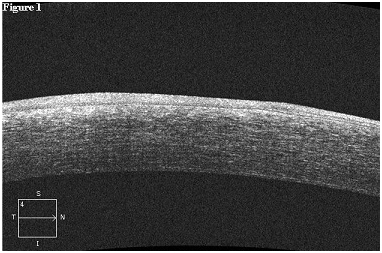

Postoperative corneal scarring on OCT resolved completely in all patients 3 months after treatment. One of the patients with proliferative diabetic retinopathy had delayed postoperative epithelial healing and underwent adjunctive treatment with autologous serum therapy to facilitate corneal re-epithelialization. None of the patients experienced the effects of aniseikonia postoperatively. None of the subjects required additional treatment with either repeat PTK or with more invasive surgery such as lamellar or penetrating keratoplasty (Figure 1-3).

Figure 1. Femtosecond Laser-assisted Phototherapeutic Keratectomy for the Treatment of Dense Corneal Scarring. The preoperative corneal optical coherence tomography of a 71 year-old female demonstrates deep and dense central corneal scarring from a previous episode of herpes simplex viral keratitis. The total corneal thickness was measured at 628 microns, and the maximum depth of the corneal scar was measured at 192 microns. The best-spectacle corrected visual acuity was 20/800.